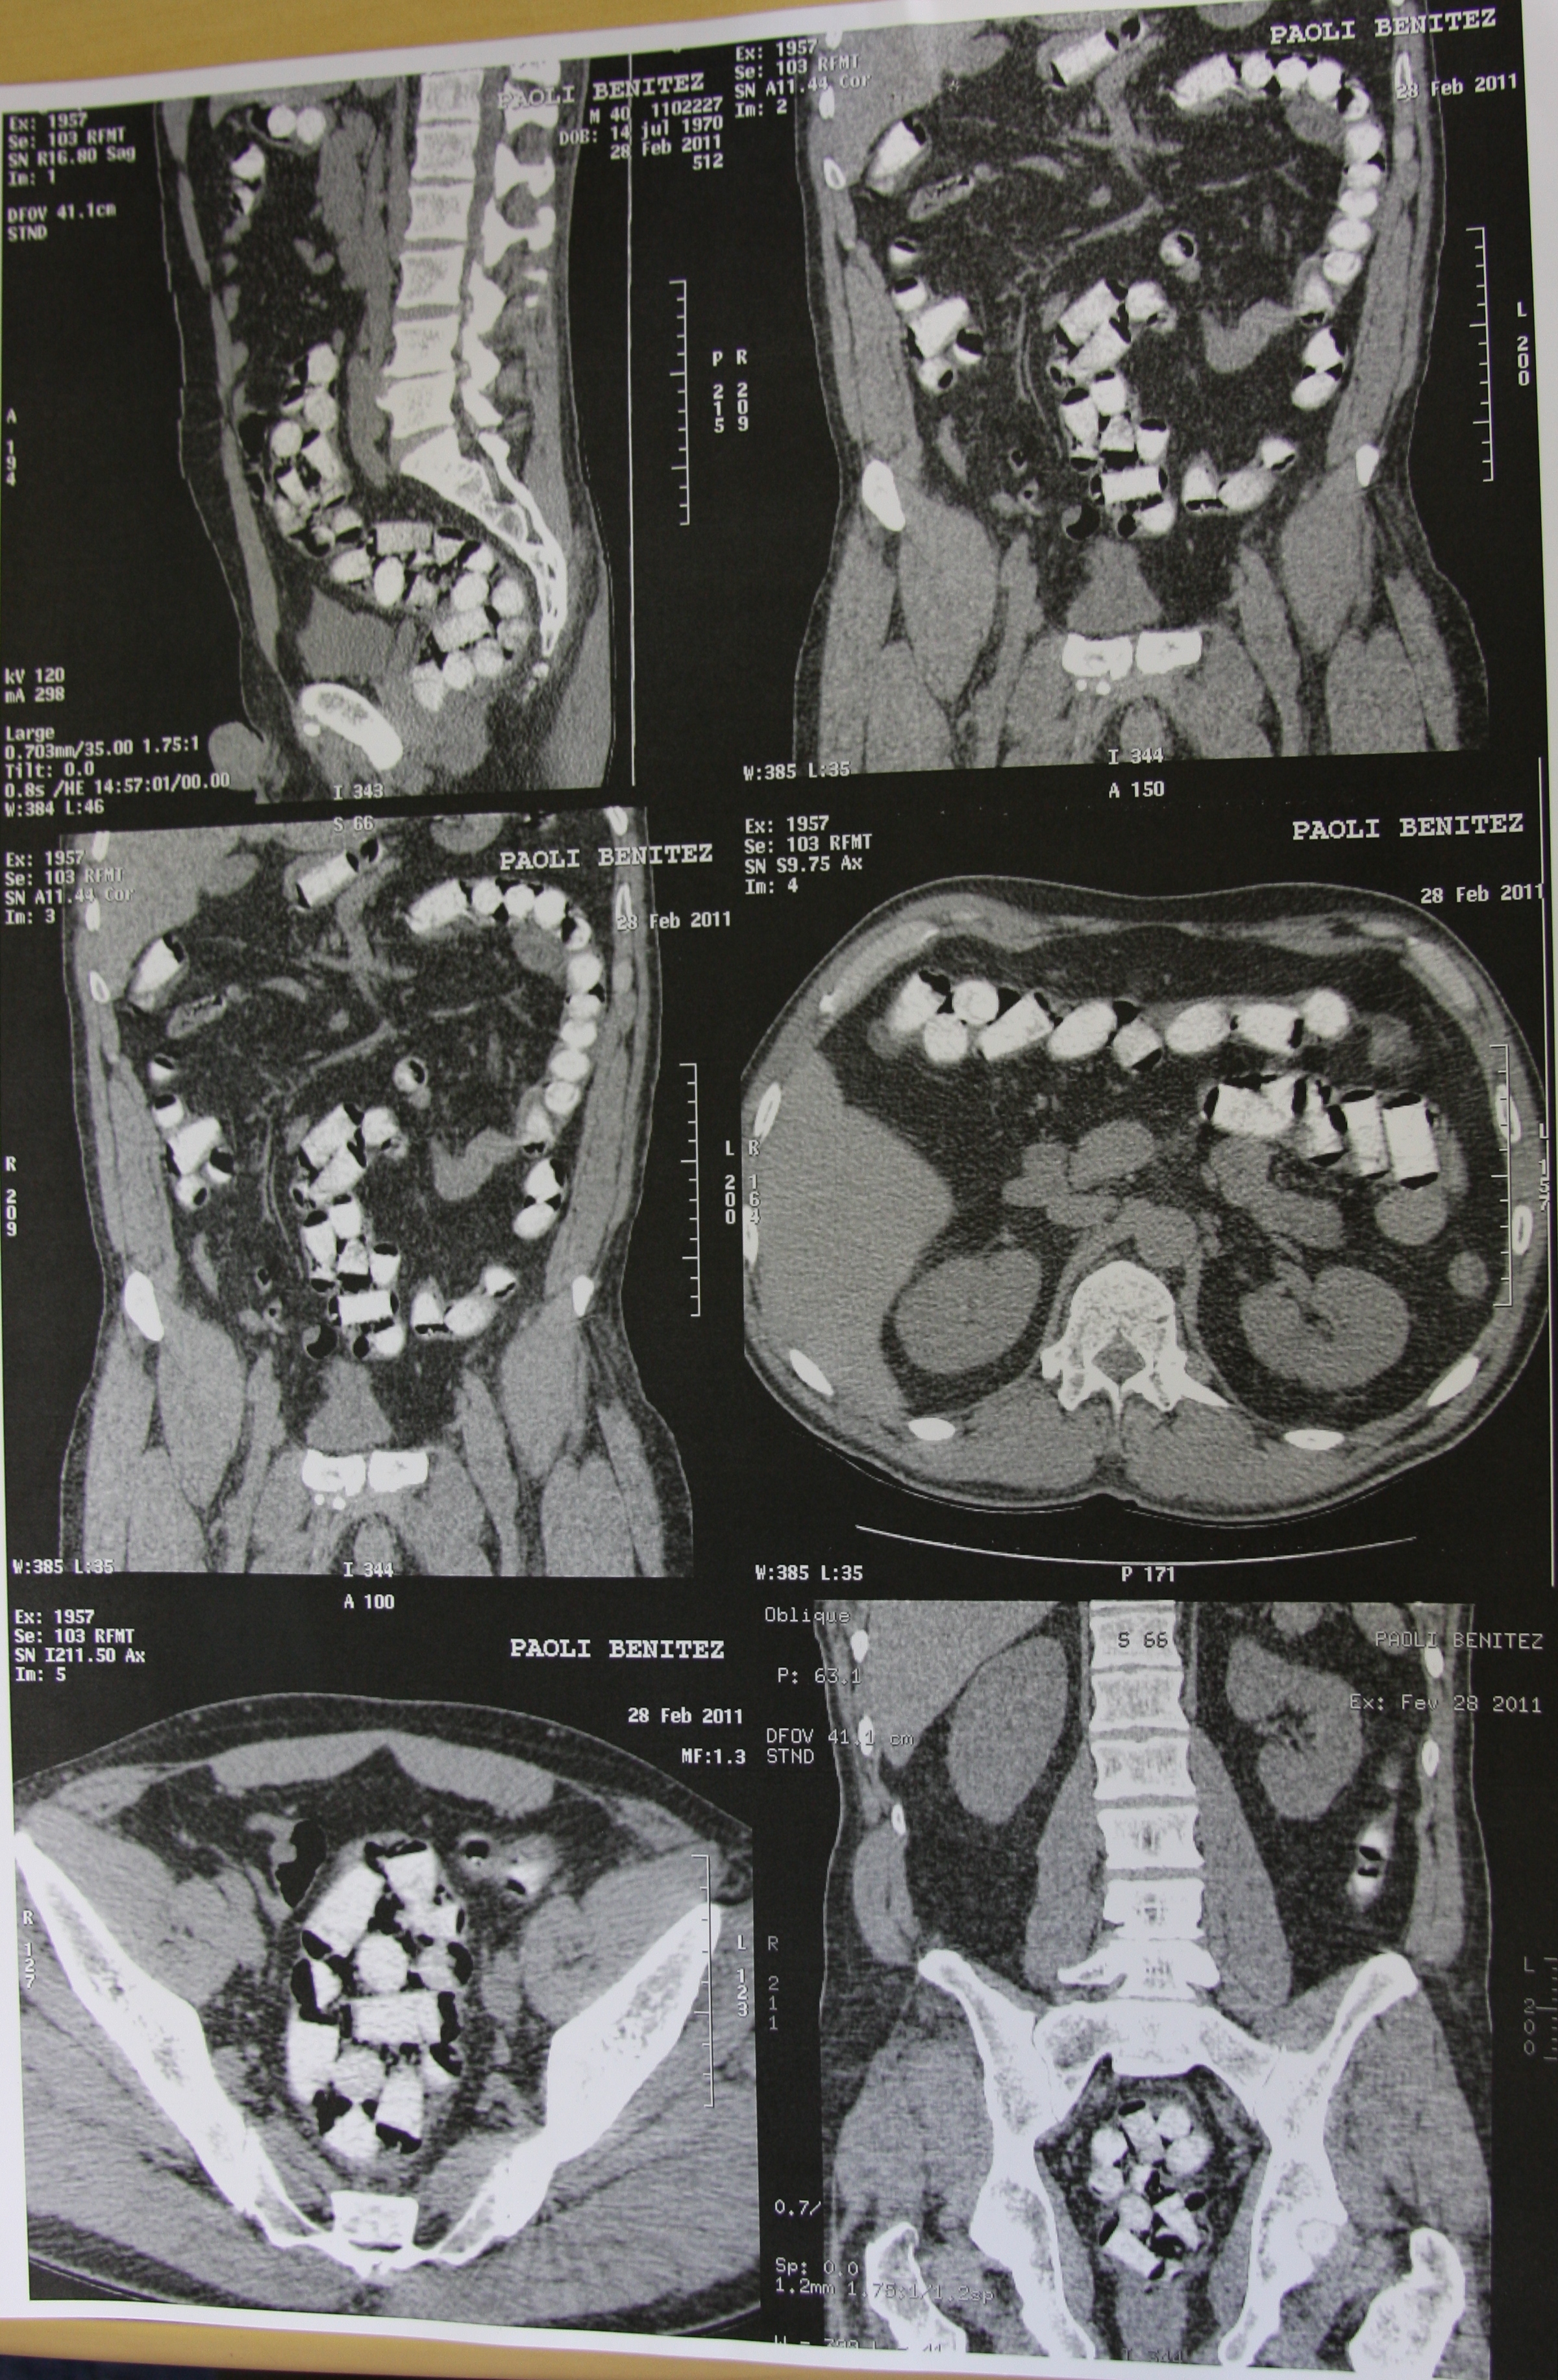

O homem foi encaminhado ao Hospital Municipal para a realização de uma tomografia computadorizada. Até esta segunda-feira foram recuperadas 24 cápsulas, que foram encaminhadas à Delegacia da Polícia Federal em Foz do Iguaçu.

As cápsulas de cocaína continham, aproximadamente, de 9 a 10 gramas da droga, totalizando quase 1,1 kg do entorpecente. Esta foi a maior apreensão de cápsulas de cocaína feita pela Polícia Federal neste ano no município.